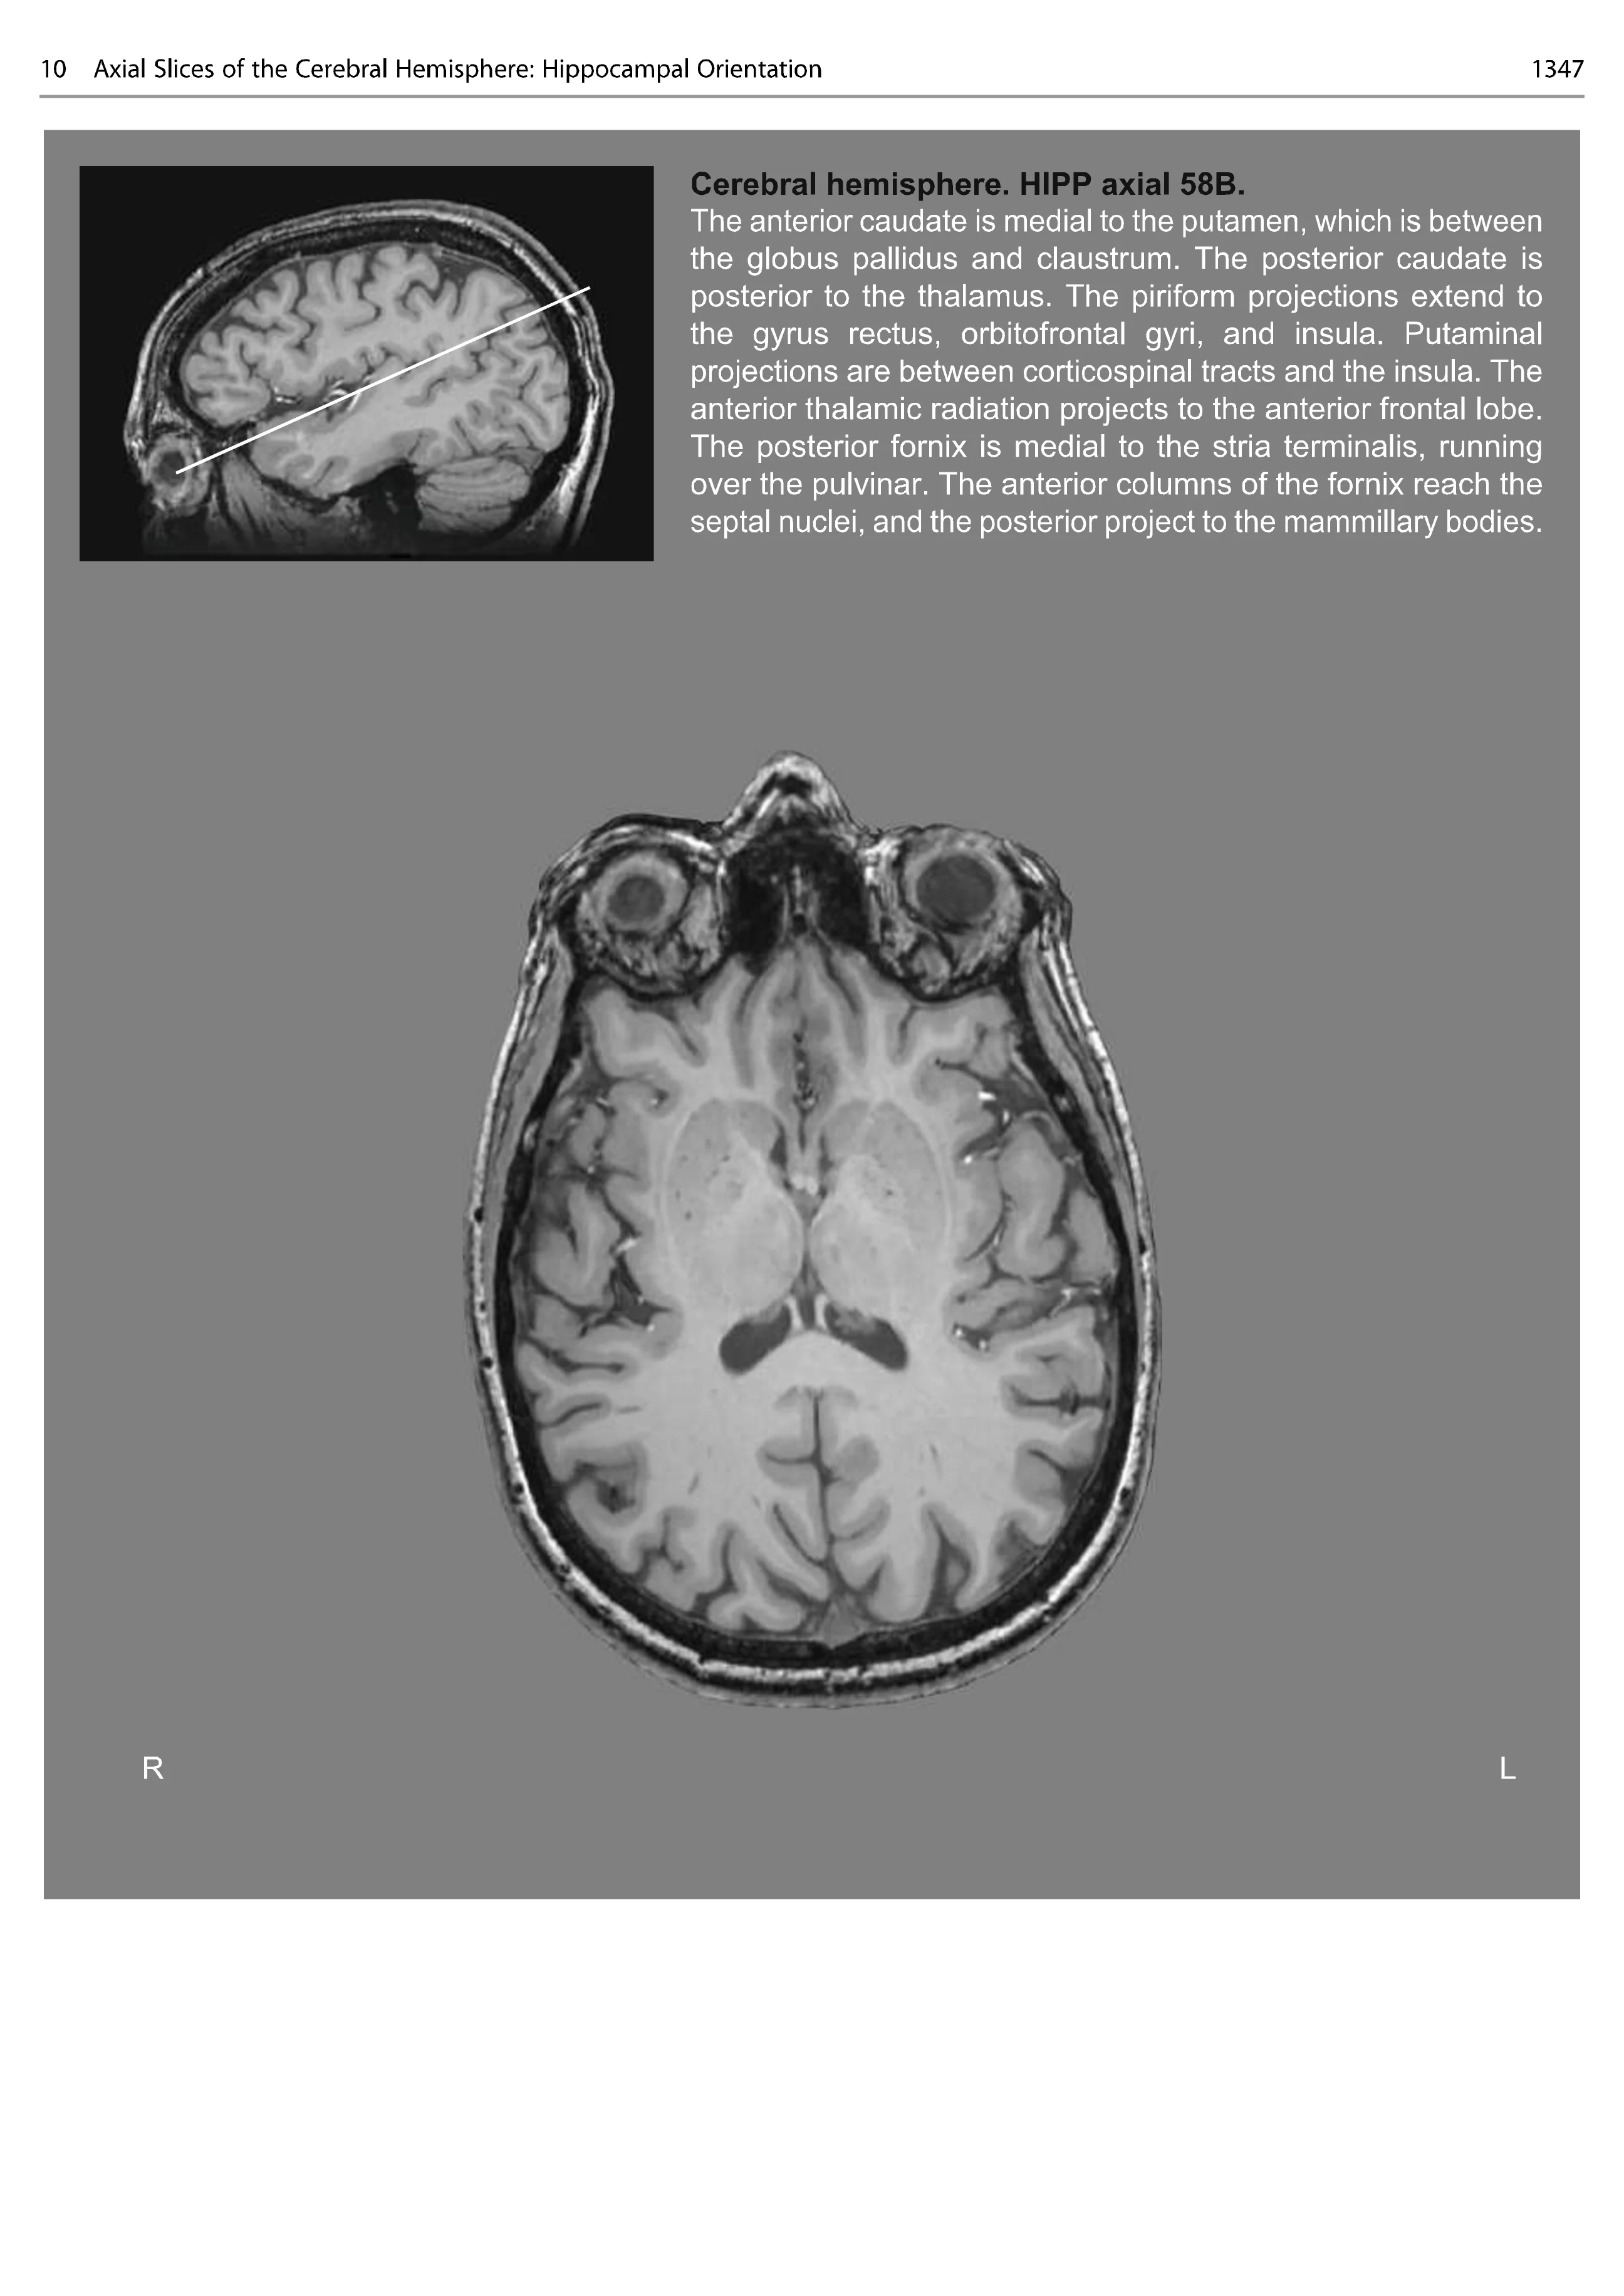

This atlas is based on a high-quality MRI of a healthy subject which resembles the type of imaging is regularly available to clinicians. It is structured in sections (cortical anatomy, subcortical anatomy, and network anatomy) that are intended to guide clinicians from the classical cortical paradigms into a network neuroscience perspective. The 2D orthogonal slices are organized in two orientations:

(A) following the plane of the anterior and posterior commissure, as has been traditionally used in stereotactic atlases

(B) following the plane of the hippocampus, as is commonly used in clinical epilepsy practice.

The second part shows the same brain cut in 2D orthogonal slices (axial, coronal, sagittal) with a raw T1-weighted image, accompanied by a labelled image showing the gross anatomy of the brain and grey matter structures and, also, the labelled white matter tracts in that slice. This is particularly relevant for neurosurgeons, who will be able to appreciate before planning a resection the relationship between each tract’s trajectory and the gray matter. This will also benefit neurologists, enabling clarity as to how single lesions can cause multiple disconnection and impact on different functions and behaviours.